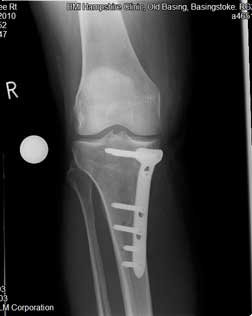

A lot of patients who require osteotomy surgery have had to live with a painful limb for a while, struggling to get around, unable to keep at active as they would have liked. This tend to lead to muscle wasting, especially in the quadriceps muscles at the front of the thigh. So the patient comes in with a varus (bow-leg) deformity, with knee pain, and significantly reduced quadriceps muscle bulk. When they have the osteotomy and the leg is re-aligned, and hopefully the muscles end up in a much more favourable position and the patient can start to do more rehab and build up those muscles. It enables the patients to strengthen their muscles. In a really varus knee [like the one in the photo] the medial ligament is not really functioning. That gentleman is beginning to get quite severe lateral knee pain, not because he has got arthritic problems in the lateral compartment but because he is getting pain from the stretching his lateral ligament. So by re-aligning the knee you can re-tension the ligaments so that a slightly stretched lateral ligament is no longer stretched and the de-functioned medial ligament begins to work again, thereby achieving a good balance.

These are the two X-rays showing the femur with the plate in position from the front (left image) and the side (right image).